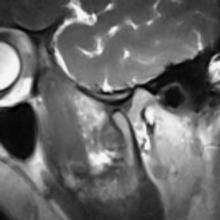

The temporomandibular joints are the dual articulation of the mandible with the skull. Each TMJ is classed as a "ginglymoarthrodial" joint since it is both a ginglymus (hinging joint) and an arthrodial (sliding) joint,[40] and involves the condylar process of the mandible below, and the articular fossa (or glenoid fossa) of the temporal bone above. Between these articular surfaces is the articular disc (or meniscus), which is a biconcave, transversely oval disc composed of dense fibrous connective tissue. Each TMJ is covered by a fibrous capsule. There are tight fibers connecting the mandible to the disc, and loose fibers which connect the disc to the temporal bone, meaning there are in effect 2 joint capsules, creating an upper joint space and a lower joint space, with the articular disc in between. The synovial membrane of the TMJ lines the inside of the fibrous capsule apart from the articular surfaces and the disc. This membrane secretes synovial fluid, which is both a lubricant to fill the joint spaces, and a means to convey nutrients to the tissues inside the joint. Behind the disc is loose vascular tissue termed the "bilaminar region" which serves as a posterior attachment for the disc and also fills with blood to fill the space created when the head of the condyle translates down the articular eminence.[41] Due to its concave shape, sometimes the articular disc is described as having an anterior band, intermediate zone and a posterior band.[42] When the mouth is opened, the initial movement of the mandibular condyle is rotational, and this involves mainly the lower joint space, and when the mouth is opened further, the movement of the condyle is translational, involving mainly the upper joint space.[43] This translation movement is achieved by the condylar head sliding down the articular eminence, which constitutes the front border of the articular fossa.[34] The function of the articular eminence is to limit the forwards movement of the condyle.[34] The ligament directly associated with the TMJ is the temporomandibular ligament, also termed the lateral ligament, which really is a thickening of the lateral aspect of the fibrous capsule.[34] The stylomandibular ligament and the sphenomandibular ligament are not directly associated with the joint capsule. Together, these ligaments act to restrict the extreme movements of the joint.[44]

Surgery

Attempts in the last decade to develop surgical treatments based on MRI and CAT scans now receive less attention. These techniques are reserved for the most difficult cases where other therapeutic modalities have failed. The American Society of Maxillofacial Surgeons recommends a conservative/non-surgical approach first. Only 20% of patients need to proceed to surgery.